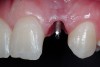

After atraumatic site preparation, two 3-mm diameter by 10-mm in length one-piece implants were seated at the No. 7 and No. 10 sites (Zimmer Dental, Carlsbad, CA) (Figure 9). Note the emergence profile formed by the esthetic recontouring of the crest of the ridge prior to implant site preparation. Confirmation of implant positioning was then verified by placing the TempStent II guide over the surgical sites (Figure 10). Ideally, because the heads of these implants are not wide and they do not lend themselves to gross preparation to reduce the facial aspect, the implants may not be suited for maxilla that has a steep angle. Minor preparation of the head can be performed facially but should be kept to a minimum.